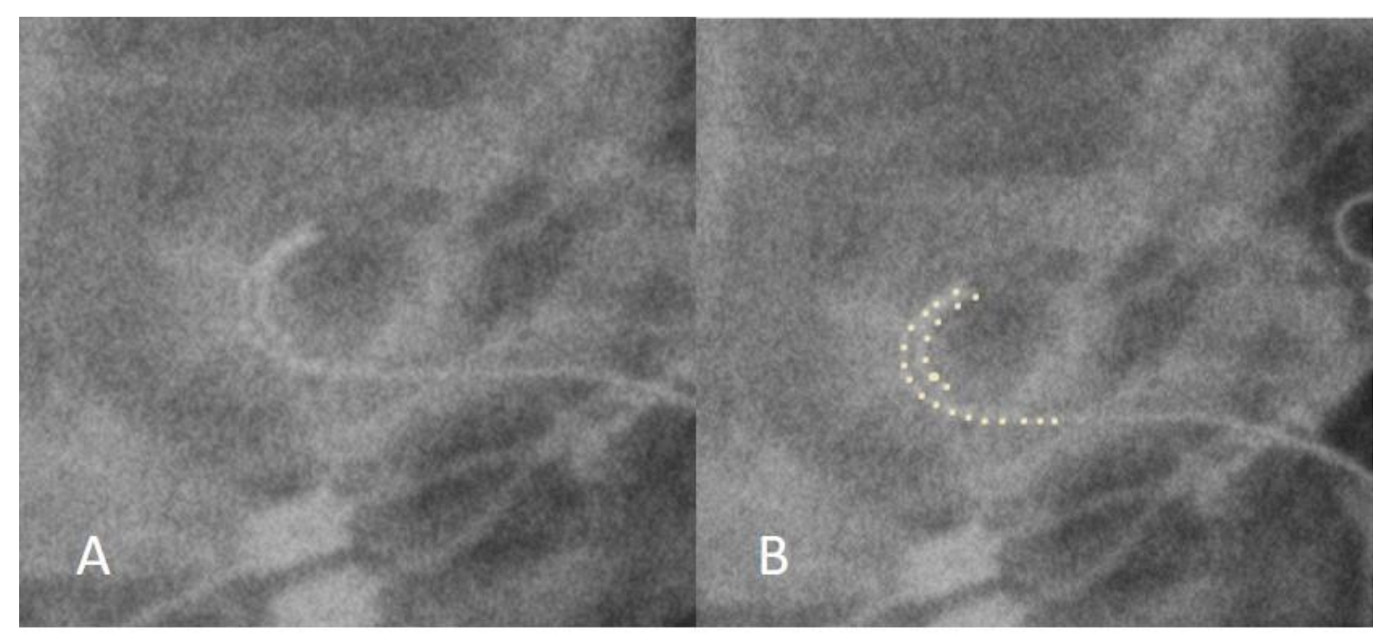

3.1. Case 1: Tip Fold-Over